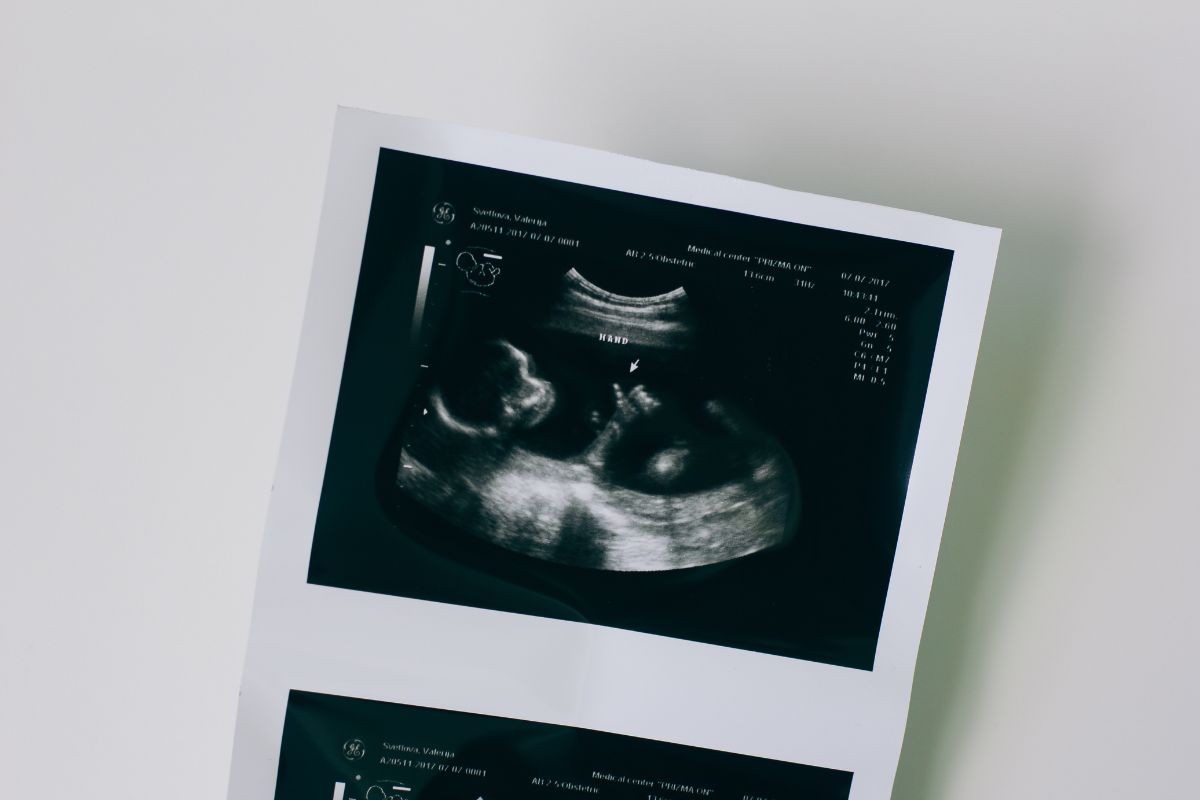

Looking for a trusted pediatric and neonatal echo specialist in Mohali? Dr Amitoz Baidwan brings 15+ years of experience in pediatric cardiology, offering safe and accurate heart screening for newborns and infants. The test is painless, non-invasive, and essential for early detection of heart conditions. Conducted in a NABH-certified, baby-friendly facility, parents can stay with their child throughout the procedure. Affordable pricing and same-day appointments available. Ensure your baby’s heart is in expert hands. Contact now: +91 90413 87878.